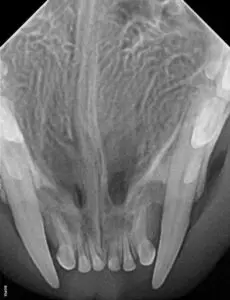

If you look closely, you can see a sore area next to the left upper canine. Normally, the lower canines would be in front of the upper canines. Even though this cat was young, the lower canines had already caused severe bone loss by putting pressure on the tissue around the upper canines, as seen in the following dental radiograph.

Fortunately, extracting the upper canines created space for the lower canines. The cat could then close her mouth without any pain.